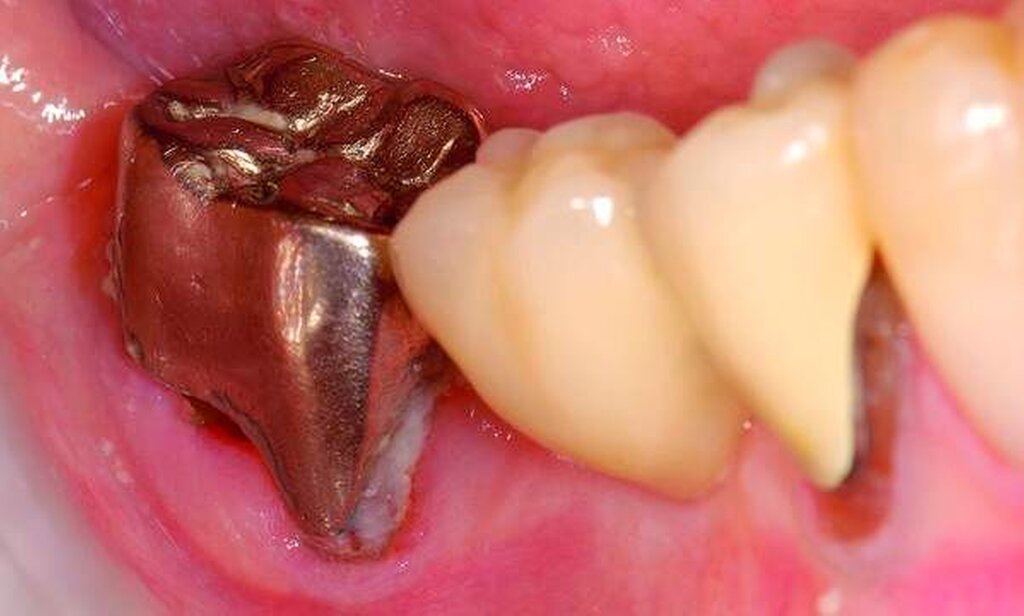

Abbildung 3: ausgedehnte Kronen- und Wurzelkaries unter einer Krone am Pfeilerzahn 47 einer seit Jahrzehnten eingegliederten Brücke von 45–47 bei einer 71-jährigen Patientin, die nach einer zerebrovaskulären Erkrankung unter Antikoagulantientherapie steht, vor etwa zwei Jahren hat sie eine Umstellung auf eine fluoridfreie Zahnpaste vorgenommen.

4. Vorgehen bei frakturierten Zahnkronen/Wurzelresten

Üblicherweise werden frakturierte Zahnkronen beziehungsweise Wurzelreste restaurativ wieder aufgebaut oder es erfolgt eine Extraktion. Im Seniorenalter erscheint es hingegen manchmal als Kompromissmaßnahme vertretbar, Wurzelreste vorerst zu belassen und etwa mit adhäsiv eingebrachtem Komposit knapp über Gingivahöhe abzudecken. Dies bietet sich vor allem dann an, wenn die Wurzelkanäle bereits obliteriert und endodontische Interventionen nicht erforderlich sind (Tabelle 4) [Staehle et al., 2017].

Abbildung 4: Anliegen eines 76,5-jährigen Patienten (Anfrage per E-Mail). Zitat: „Mich plagt eine … Entzündung des Mundraums, die auch das Zahnfleisch meiner Zahnstummel angreift, weshalb ich nur noch Breiartiges zu essen vermag. Ein Angsthase wie ich geht zum Zahnarzt NUR unter dem Eindruck akuter Schmerzen!“

Damit wird die Hygienefähigkeit zumindest partiell verbessert und Spielraum für künftige Planungen und Vorgehensweisen unter besseren Bedingungen belassen. Das Procedere ist in den Abbildungen 4 und 5 beschrieben. Bei dem in Abbildung 4 vorgestellten Patienten lag eine Oralphobie im Seniorenalter vor. Die Verlaufsbeschreibung macht deutlich, dass selbst im fortgeschrittenen Alter eine Adaptation an zahnärztliche Interventionen im Einzelfall noch möglich ist.